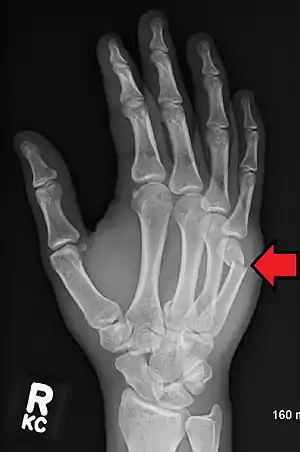

Diagnosis by a doctor’s examination is the most common, often confirmed by x-rays. X-ray is used to display the fracture and the angulations of the fracture. A CT scan may be done in very rare cases to provide a more detailed picture.[8]

Boxer fracture

Boxer fracture of the 4th and 5th knuckles